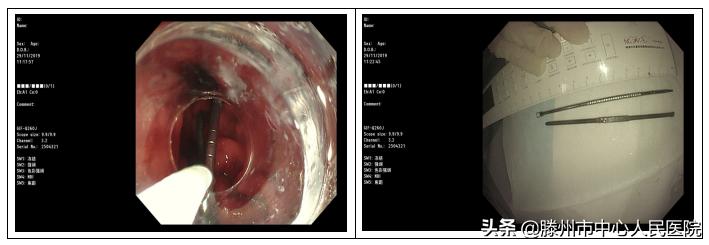

李曙晖主任接诊后给予行急诊胃镜检查,常规进境至十二指肠降段后未发现异物,继续寻腔进境,将镜身整体插入后,才发现假牙停留于十二指肠水平部,予以异物钳夹住牙套金属部后,发现牙套整体紧紧嵌顿于憩室内,无法直接拖出,胃镜前段加装透明帽后,再次尝试,异物钳将牙套金属尖端拖入透明帽后,反复旋转镜身,使牙套逐步脱出憩室,最终将其完整取出体外。此时发现该牙套形态奇特,棱角锐利,加之嵌顿于憩室内,造成长时间潴留于十二指肠内,并给胃镜下取出术带来极大困难,如不及时取出,该牙套可能造成十二指肠局部溃疡形成,肠壁穿孔可能。该牙套的成功取出,为患者免除了开腹手术之痛,得到了患者的高度认可。